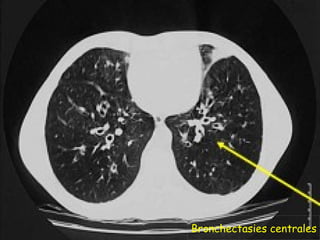

 TDM thoracique :

   Examen de référence pour mev des DDB proximales

(critère majeur de Dic) et des impactions mucoides .

   Permet de voir les images associées : infiltrats

labiles, atélectasies, aspect d’emphysème.

   Plus sensible et plus précoce pour Dic des fibroses

pulmonaires.

Bronchectasies centrales

Impactions mucoides

DDB cylindriques et kystiques proximales prédominant aux

lobes sup, avec trbles ventilatoires et bronchomucocèles.